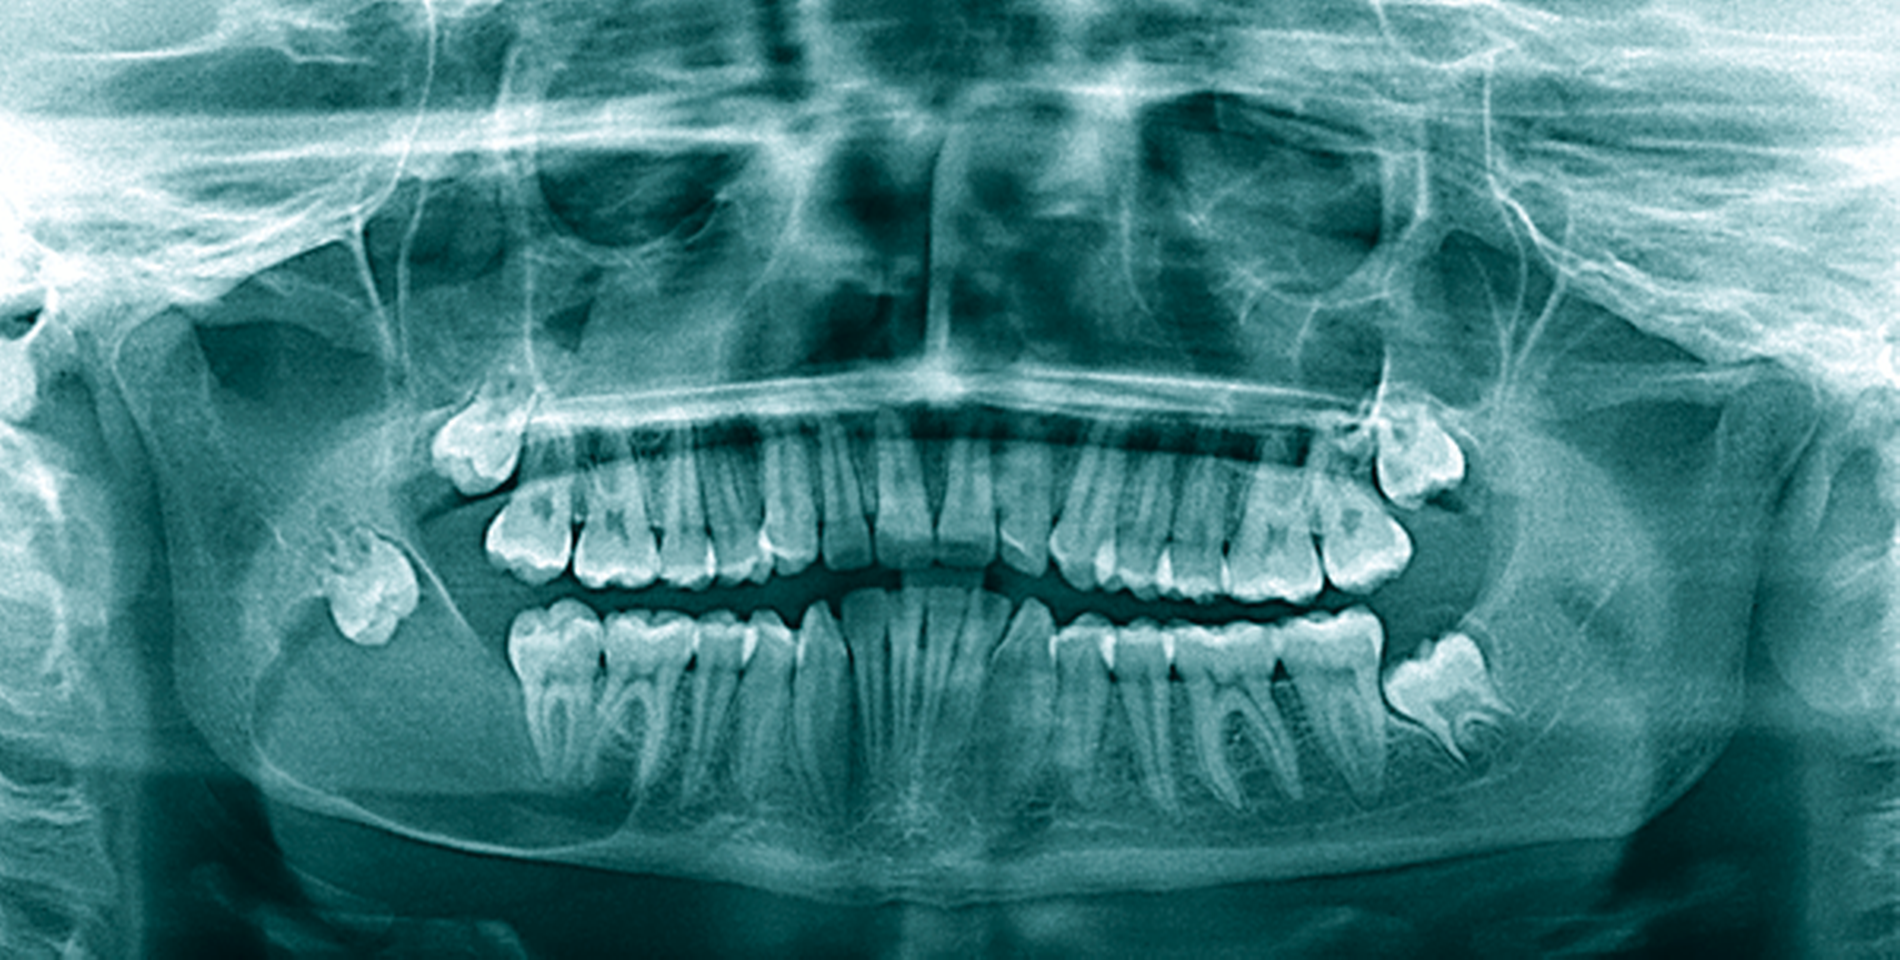

Ein 14-jähriger Patient wurde mit dem Zufallsbefund einer zystischen Raumforderung im Bereich des Kieferwinkels rechts in unser MVZ überwiesen (Abbildung 5a). Aufgrund der Ausdehnung mit Affektion des N. alveolaris inferior sowie der Wurzelspitzen der Zähne 47 und 46 wurde sich nach Abwägung der perioperativen Risiken in enger Absprache mit den Eltern und dem Patienten gegen eine primäre Zystektomie mit Entfernung des extrem verlagerten Zahnes 48 entschieden. Eltern und Patient bevorzugten – trotz absehbar längerer Behandlungszeit – die primäre Verkleinerung der Zyste mittels Obturatortherapie.

Das histopathologische Gutachten ergab die Diagnose einer Keratozyste. Daher erfolgte bereits nach drei Monaten eine Verlaufskontrolle mittels OPG, um ein Ansprechen auf die Therapie sicherzustellen. Nach sechs Monaten bereits war die Ausdehnung der Keratozyste so weit regredient, dass die vollständige Entfernung des Restbefunds sowie des Zahnes 48 mit risikoarmem Anfrischen des umliegenden Knochens in ambulanter ITN erfolgen konnte (Abbildung 5b). Die Zähne 18, 28 und 38 wurden dabei ebenfalls entfernt. Die Sensibilität der Unterlippe sowie der Zähne 46 und 47 konnte erhalten werden. Die Verlaufskontrolle nach einem weiteren halben Jahr zeigte eine gute knöcherne Durchbauung des ehemaligen Defekts im Bereich des Kieferwinkels rechts und der Patient blieb weiterhin beschwerdefrei (Abbildung 5c).